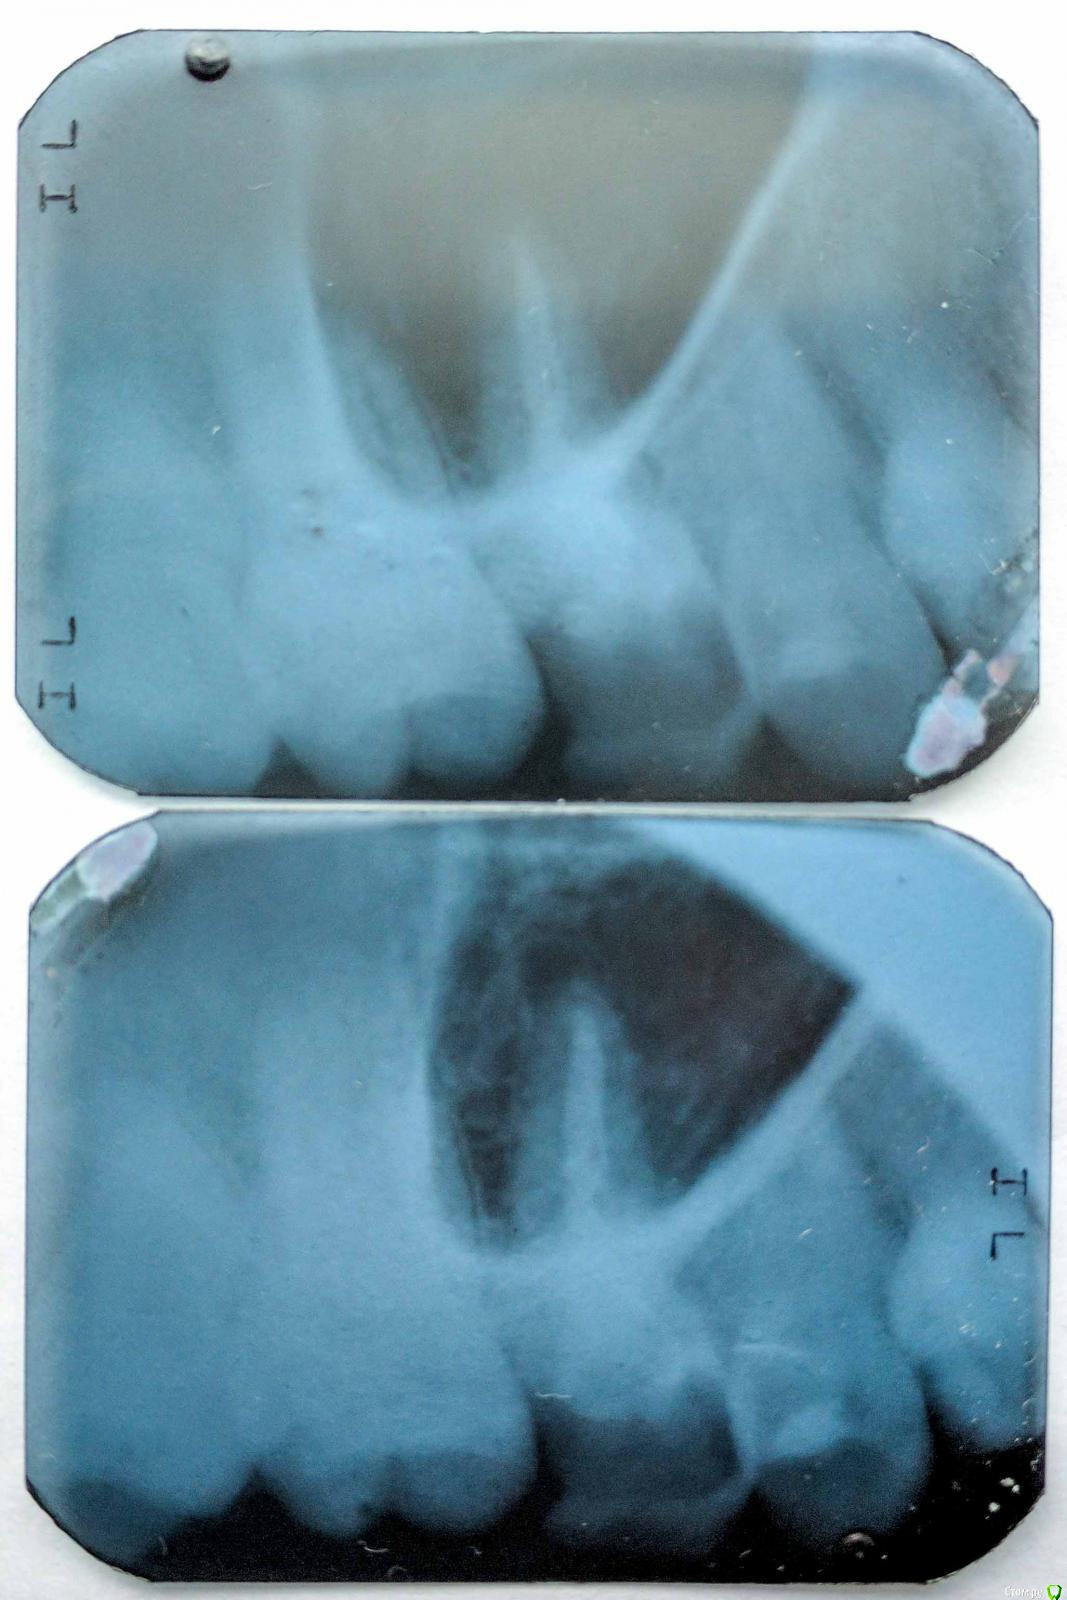

Баурсак Опубликовано 27 июня, 2017 Поделиться Опубликовано 27 июня, 2017 Здравствуйте, прошу помощи.Панарамный снимок сделан 14.04.2017, при планировании лечения зуба 25 (стоит пломба, чувствительность к холодному и горячему).Лечить еще не ходил и вот только собираюсь.Для надежности сегодня сходил и сделал снимки отдельных зубов, того же 25 и еще 16 (тоже планируется лечение, зуб мертвый и начал крошиться).На одиночном снимке зуба 16 видна какая то темная область (снимали его два раза для исключения ошибки). Я очень переживаю, на апрельском снимке темной зоны не видно. Десна в том месте не болит, зуб 16 потемневший, рядом с десной имеет темное обрамление.Подскажите пожалуйста что на снимке? Ссылка на комментарий

shishok Опубликовано 27 июня, 2017 Поделиться Опубликовано 27 июня, 2017 На отдельных снимках наслаивается проекция гайморовой пазухи. Ссылка на комментарий